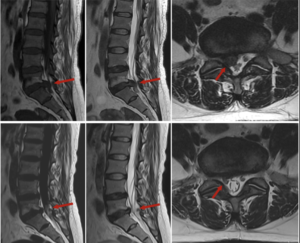

Как изглежда дисковата херния на MRI

MRI е едно от най-често използваните образни изследвания, когато трябва да се оцени състоянието на междупрешленните дискове и нервните структури. В MRI описанията често могат да се срещнат термини като:

дегенерация на диска

булджинг диск

дискова протрузия

дискова екструзия

секвестрация

притискане на нервно коренче

стеснение на гръбначния канал

фораминална стеноза

Образното изследване може да даде важна информация за формата на диска, неговата височина, наличието на издуване или херниране, както и за евентуален контакт с нервни структури. Въпреки това MRI трябва винаги да се разглежда заедно със симптомите и функционалната оценка на пациента.

Оценка на състоянието при дискова херния

При работа с пациенти с дискова херния е важно да не се гледа само образната находка. От значение е и как се движи тялото, какви симптоми предизвикват определени движения, каква е подвижността на гръбначния стълб и как реагират меките тъкани и нервните структури.